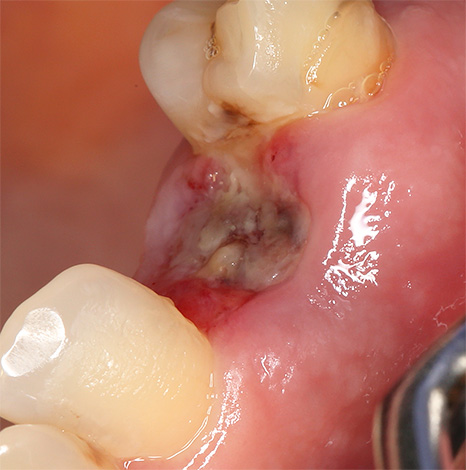

A foto a seguir mostra um exemplo de phlegmon odontogênico:

É por isso que é tão importante reconhecer o problema a tempo. Se, depois de arrancar um dente, o buraco estiver podre por algum motivo, não espere até que tudo resolva por si só - você precisará usar todos os meios possíveis para interromper essa complicação.